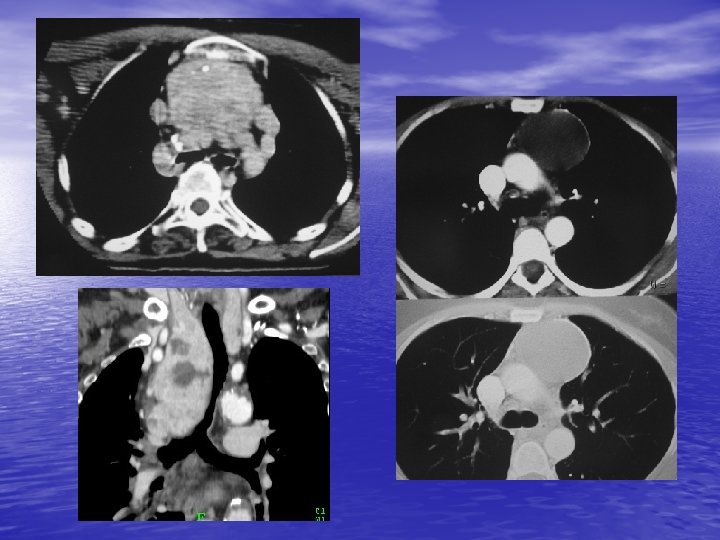

2. 2. TDM - Reconnaissance de la nature vasculaire d’une masse médiastinale. - Détection de petites tumeurs (supérieure au cliché rx thoracique). - Localisation des tumeurs : 8 compartiments. - Reconnaissance du contenu de la tumeur : hypervascularisation (goitre, thymome, adénome parathyroïdien, paragangliome, …) calcifications inconstantes (goitre, ADP, thymome, tumeurs nerveuses, …), liquidiennes (kystes dérivés de l’intestin primitif, lymphangiome, thymome), graisseuse (lipome, liposarcome).

- Recherche de signes de malignité : lésion mal - limitée, densification de la graisse. Bilan préopératoire. Guidage d’une biopsie.

4. MASSES DU MEDIASTIN MOYEN 4. 1. Kyste bronchogénique - 10 % des tumeurs du médiastin. - Bourgeon aberrant détaché de l’ébauche trachéo - -bronchique. Diagnostic fortuit. Rond ou ovale, parfois paroi calcifiée. Densité parfois élevée (lait calcique).

5. MASSE DU MEDIASTIN POSTERIEUR 5. 1. Tumeurs neurogènes - Tumeur des nerfs périphériques (schwannome, neurofibrome), des ganglions sympathiques (ganglioneurome, neuroblastome), paraganglionnaires (chémodectome). - ++ gouttières costo-vertébrales, parfois calcifications, lésions osseuses associées évocatrices (trou de conjugaison élargi). - Rôle ++ de l’I. R. M. pour le bilan (recherche de prolongement intra-rachidien).